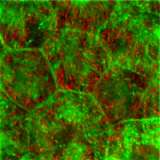

Primary culture of RPE cells

Fig. 2. Primary culture of RPE cells, showing the melanosome autofluorescence in red, due to excitation with 633-nm light, and phalloidin labeling of actin filaments in green. From Gibbs et al., 2009.